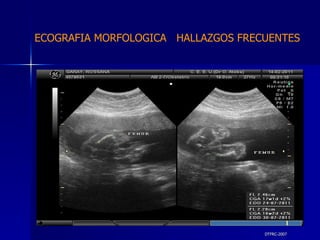

DTFRC-2007 MIEMBROS   PROTOCOLO  DE ESTUDIO  ECOGRAFICO DE LA ANATONIA  FETAL

DTFRC-2007 ECOGRAFIA MORFOLOGICA  HALLAZGOS FRECUENTES   GENITOURINARIA DISPLASIA RENAL MULTIQUISTICA  3 HIDRONEFROSIS  2 QUISTE DE OVARIO FETAL  1 SISTEMA DIGESTIVO DILATACION INTESTINAL  2  SISTEMA ESQUELETICO   PIE BOT  2  20 % 6 % 6 %